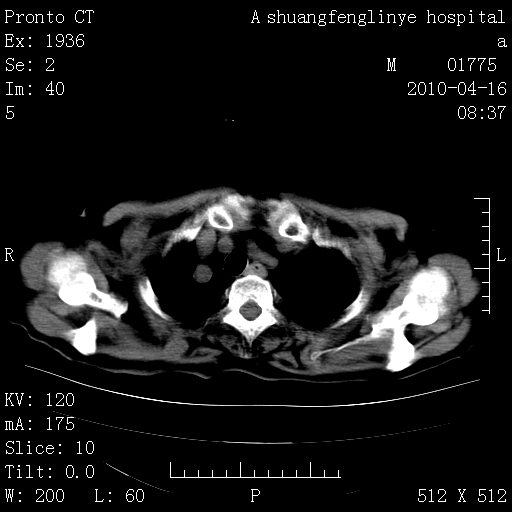

标题: CT25784:咳痰、请会诊!结核?

慢支肺气肿,左上陈旧性结核,主动脉冠脉钙化

典型 夹层动脉瘤。 内膜瓣钙化移位

1)左肺上叶结核(纤维、增殖病灶)。2)冠状动脉及主动脉钙化。

1)左肺上叶结核(纤维、增殖病灶)。2)冠状动脉及主动脉钙化。肺动脉高压